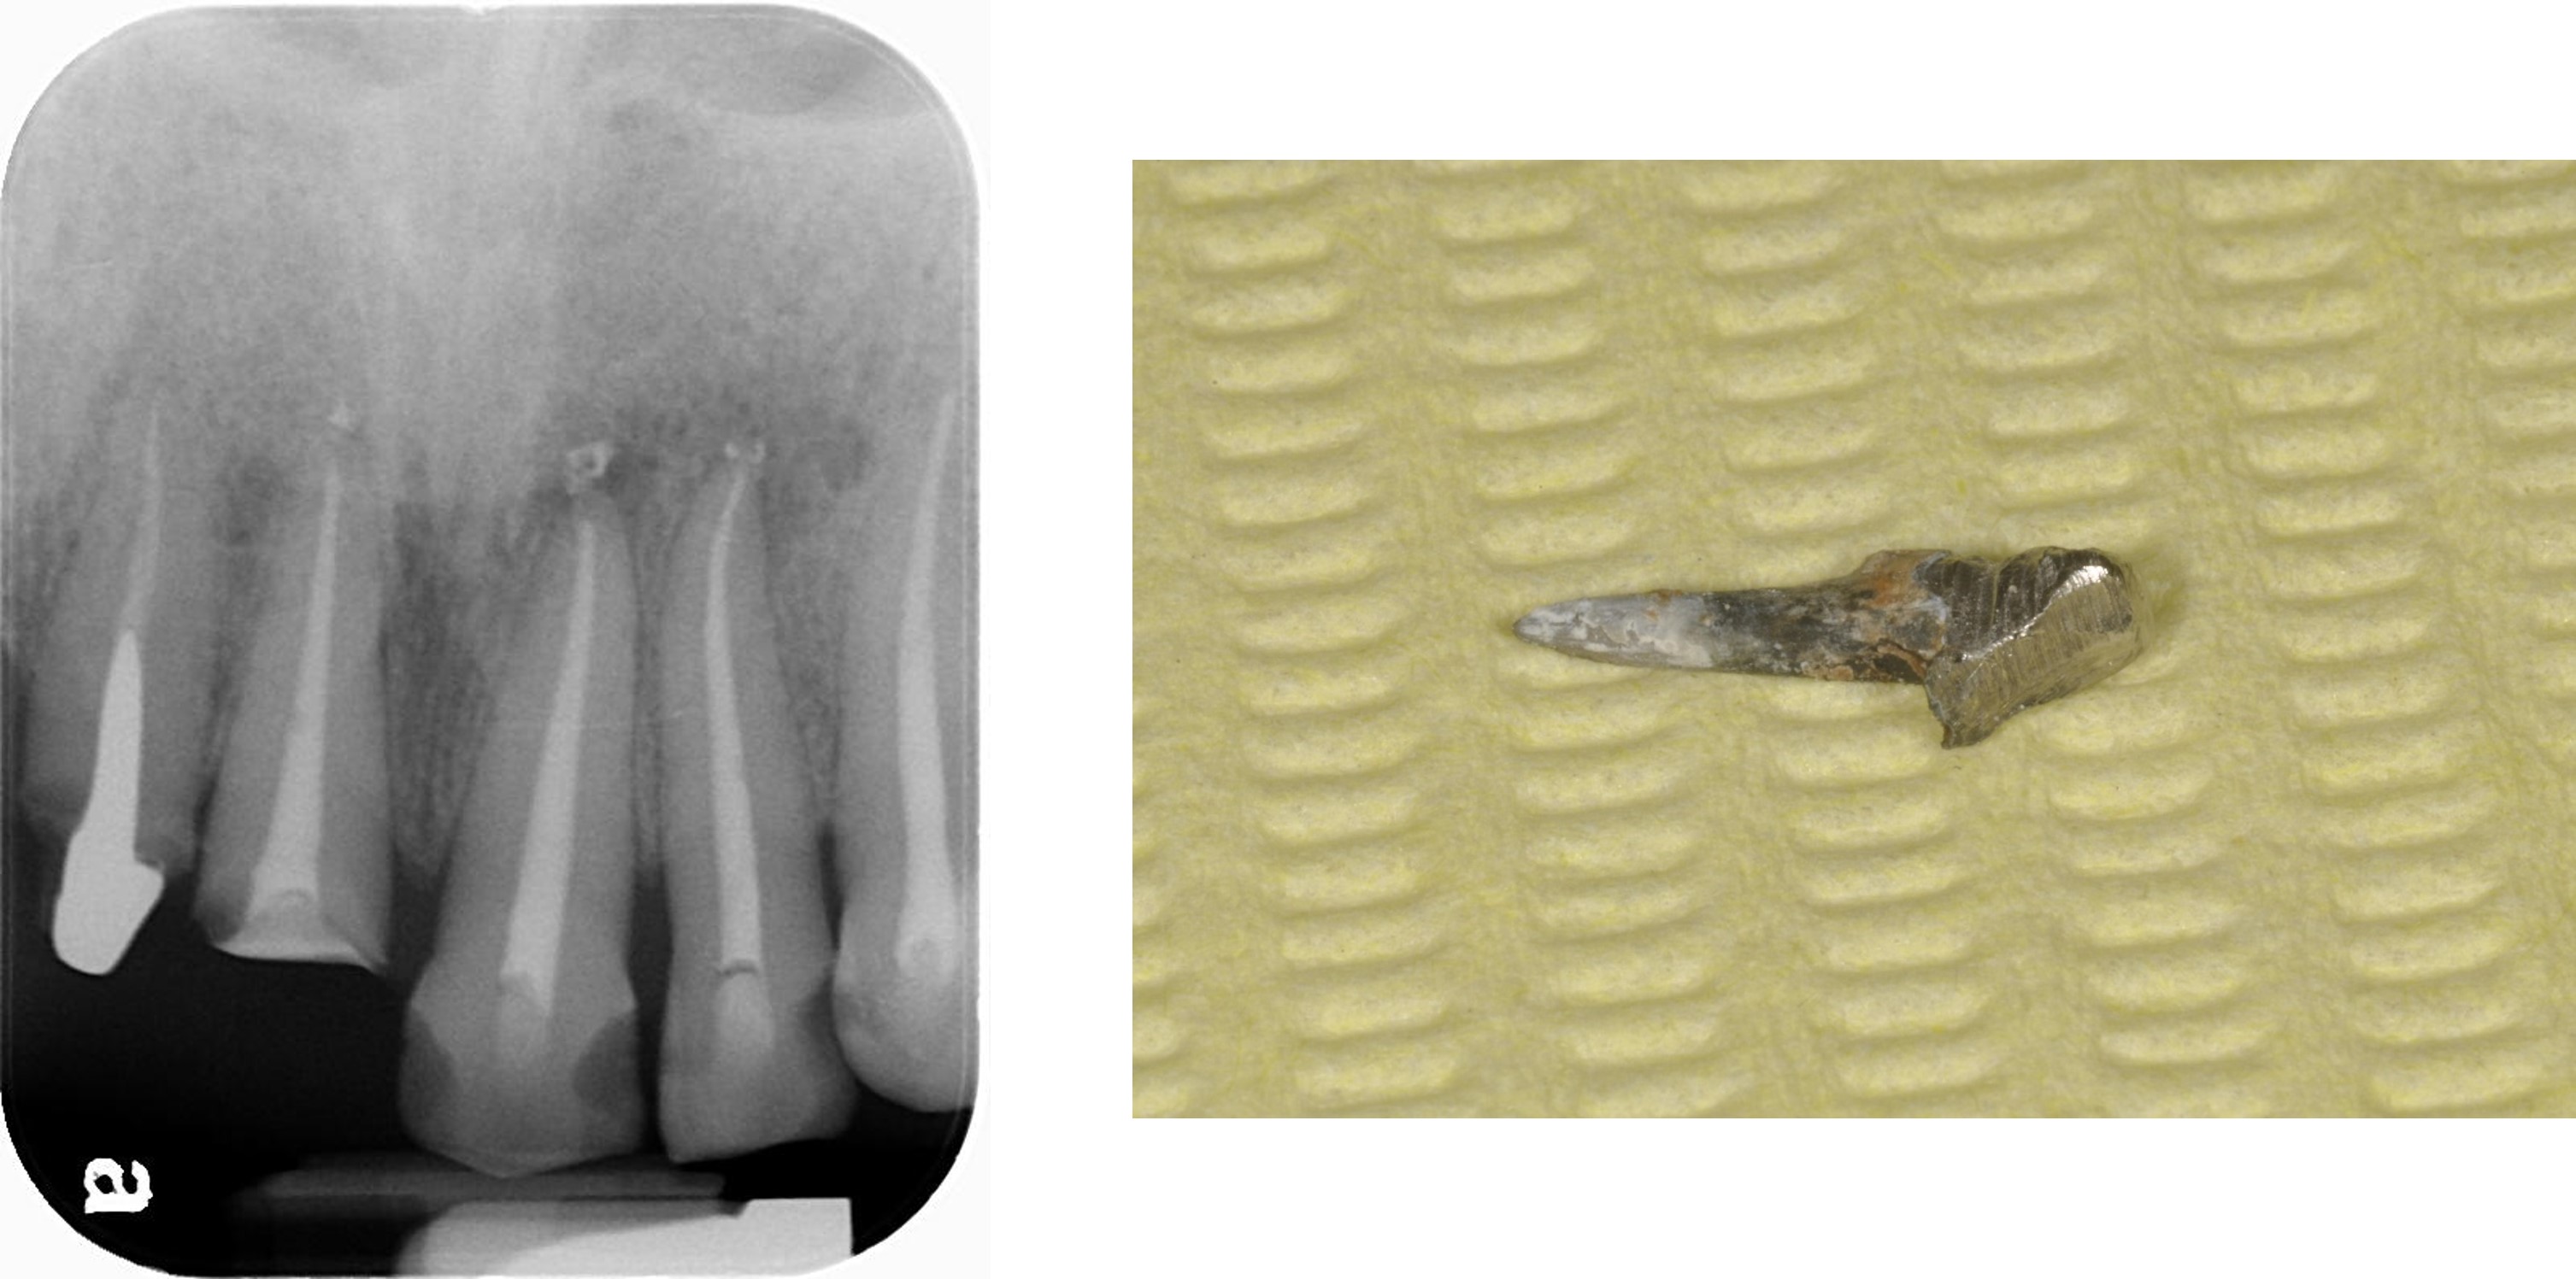

移除舊釘柱

膺復前評估